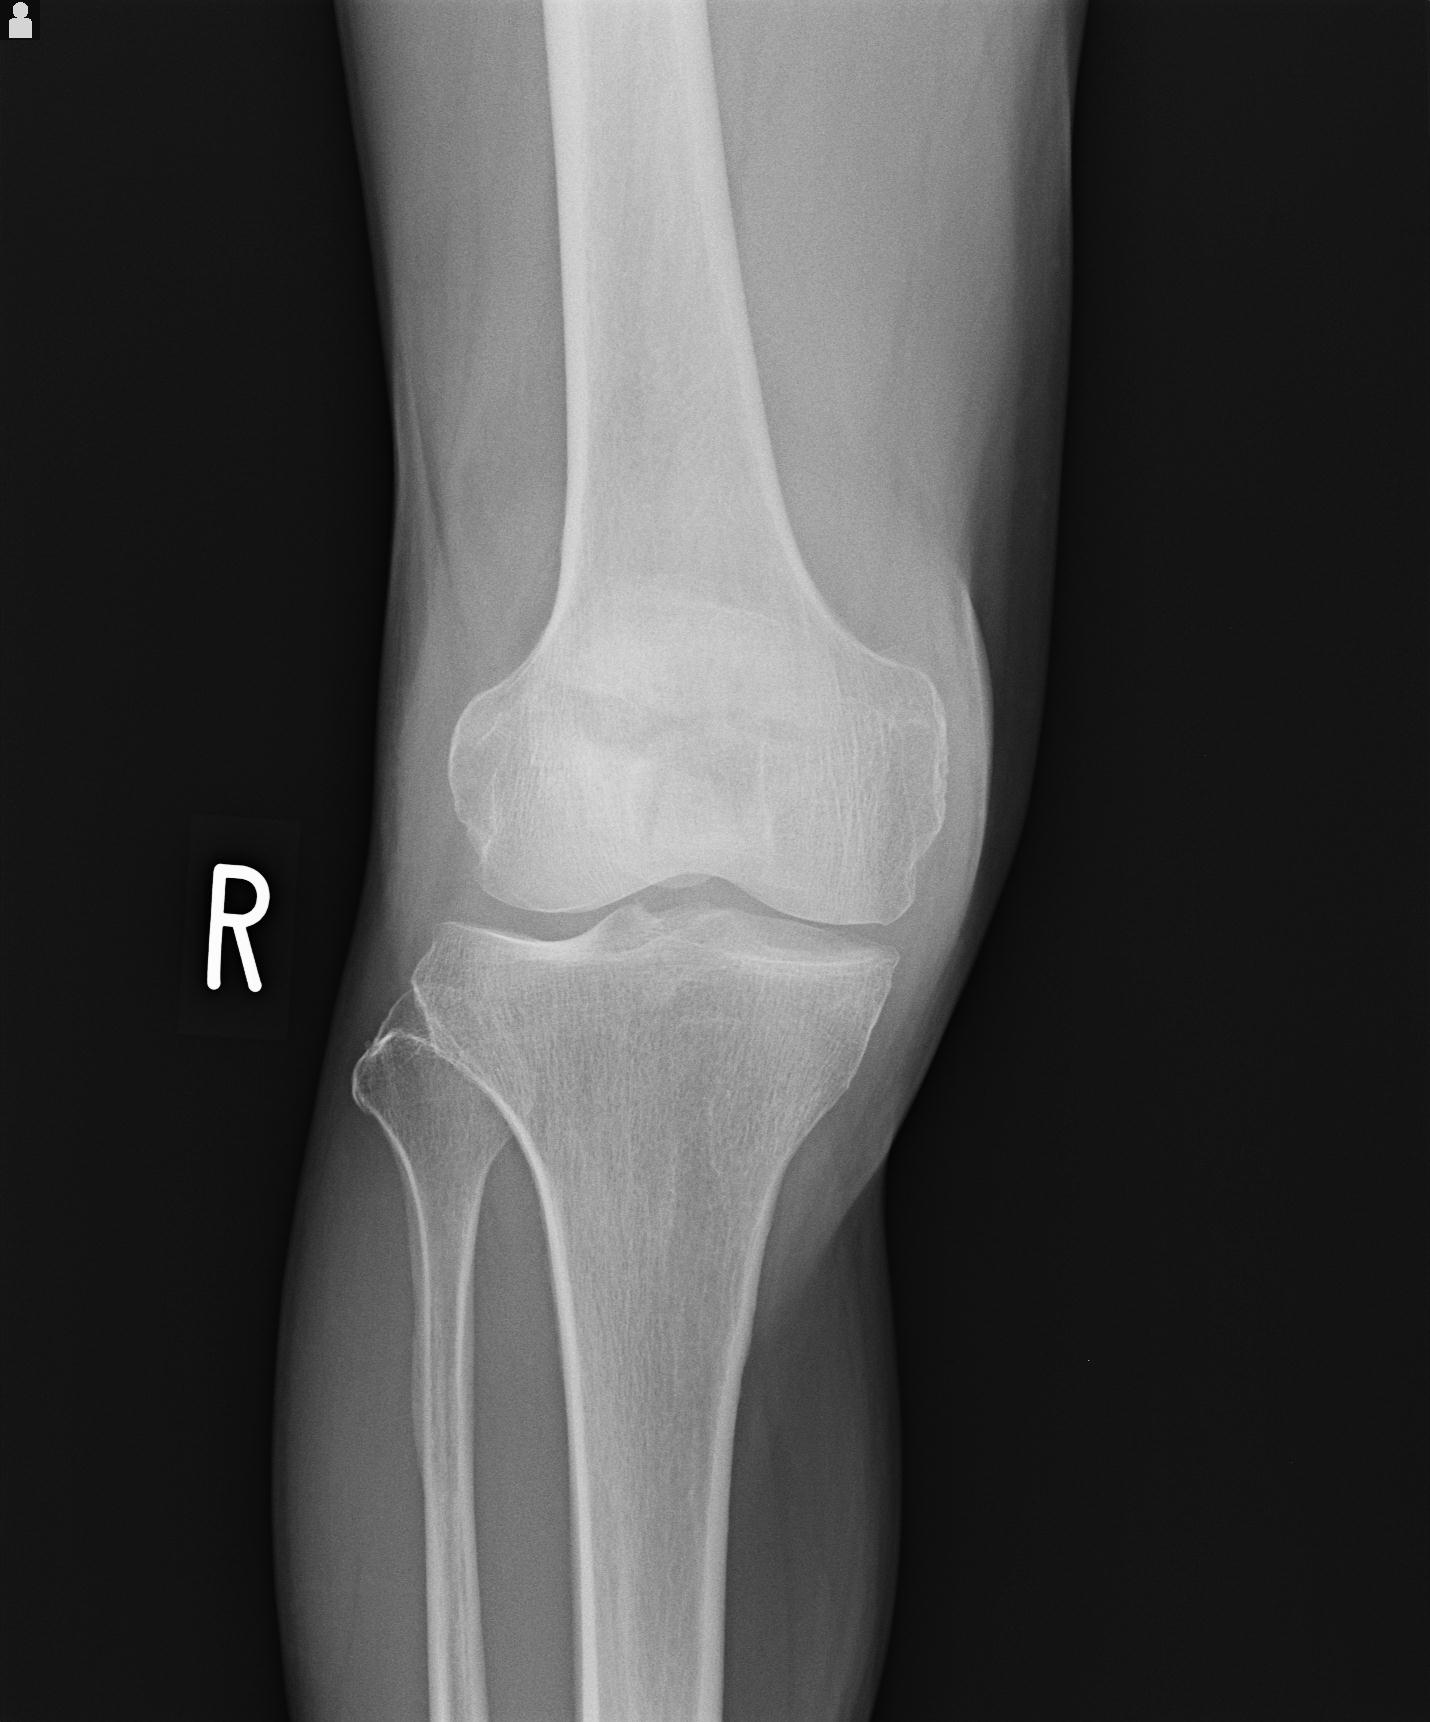

49554 3/13 膝 4R 3/16 4R 1/18 2R 78歳男性 膝蓋骨骨折